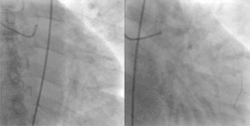

Röntgenopname van het hart voor en na een PCI van de LAD (afdalende tak van de linker kransslagader